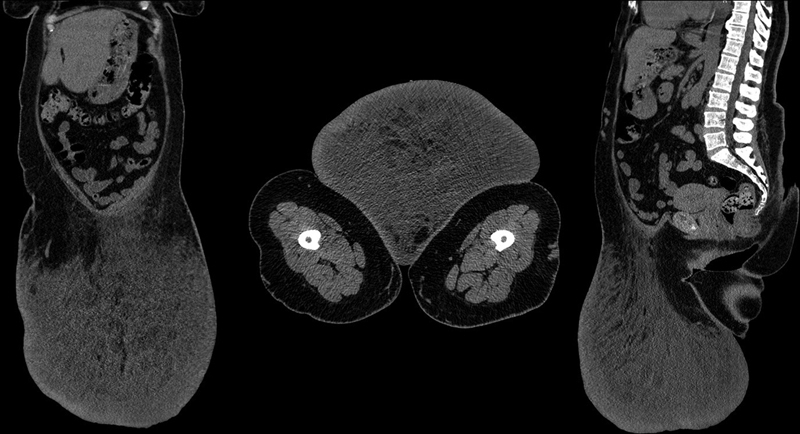

大面积局部淋巴水肿(MLL)是一种由淋巴管阻塞引起的罕见疾病,具有特殊的临床形态学和放射学特征。病态肥胖症患者主要受 MLL 影响。淋巴水肿很容易与软组织肉瘤混淆,需要进行鉴别诊断,既要考虑 MLL 的可能性,也要考虑软组织的癌变表现。导致大量淋巴水肿的可能原因包括创伤、手术和甲状腺功能减退。本报告是俄罗斯联邦首例通过手术治疗的 MLL 病例。本文讨论了 MLL 的详细计算机断层扫描(CT)特征和电子显微镜图片。一名 50 岁女性(体重指数为 43 kg/m 2)因腹壁前部出现 MLL 而入院接受手术治疗。其质量为 22.16 千克。切除肿块的形态学研究证实了 MLL 的诊断。我们回顾了 MLL 的病因、临床表现、诊断和治疗。我们还进行了一项电子显微镜研究,发现了间质卡贾尔样细胞端细胞,这是以前在 MLL 病例中没有发现过的。我们在文献中没有找到类似的发现。对 MLL 组织样本进行超微结构检查可能会进一步促进对 MLL 发病机制的了解。

Massive localized lymphedema (MLL) is a rare disease caused by the obstruction of lymphatic vessels with specific clinical morphological and radiological characteristics. People with morbid obesity are mainly affected by MLL. Lymphedema is easily confused with soft tissue sarcoma and requires differential diagnosis, both the possibility of an MLL and also carcinoma manifestations in the soft tissues. The possible causes of massive lymphedema include trauma, surgery, and hypothyroidism. This report is the first case of MLL treated surgically in the Russian Federation. Detailed computed tomography (CT) characteristics and an electron microscope picture of MLL are discussed. A 50-year-old woman (body mass index of 43 kg/m 2 ) with MLL arising from the anterior abdominal wall was admitted to the hospital for surgical treatment. Its mass was 22.16 kg. A morphological study of the resected mass confirmed the diagnosis of MLL. We review etiology, clinical presentation, diagnosis, and treatment of MLL. We also performed an electron-microscopic study that revealed interstitial Cajal-like cells telocytes not previously described in MLL cases. We did not find similar findings in the literature. It is possible that the conduction of an ultrastructural examination of MLL tissue samples will further contribute to the understanding of MLL pathogenesis.